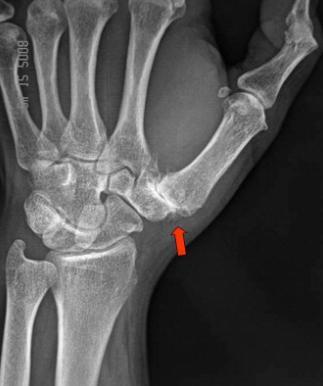

Thumb arthritis refers to degeneration of the carpometacarpal (CMC) joint (sometimes called the basal joint) at the base of the thumb.1 The CMC joint is formed where the thumb metacarpal bone meets the small wrist bone called the trapezium.1

Imaging: Your surgeon may request X-rays of the hand and thumb base.8